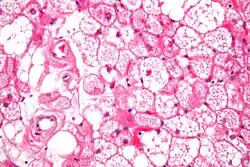

Hibernoma (intermediate magnification).

The tumors histologically resemble brown fat. There are four histologic types recognized, but one is the most frequently seen (typical). There is a background of rich vascularity.

- Lobular type: Variable degrees of differentiation of uniform, round to oval cells with granular eosinophilic cells with prominent borders, alternating with coarsely multivacuolated fat cells (pale cells). There are usually small centrally placed nuclei without pleomorphism. The cells have large cytoplasmic lipid droplets interspersed throughout.[4][5]